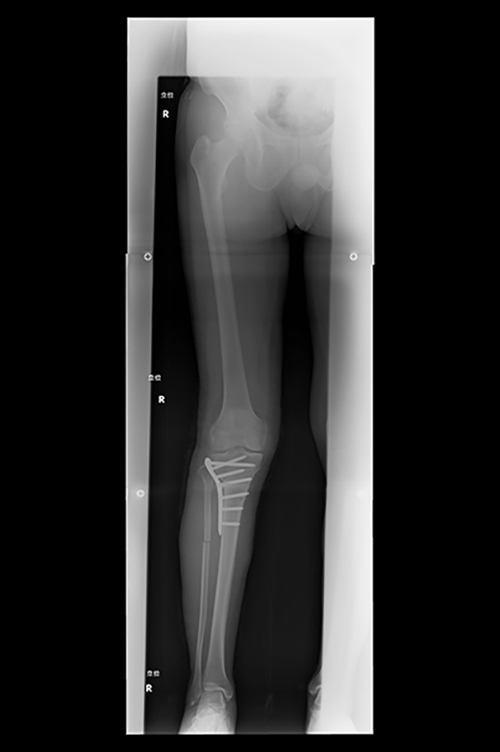

骨切り術(高位脛骨骨切り術)

HTOの術前、術後